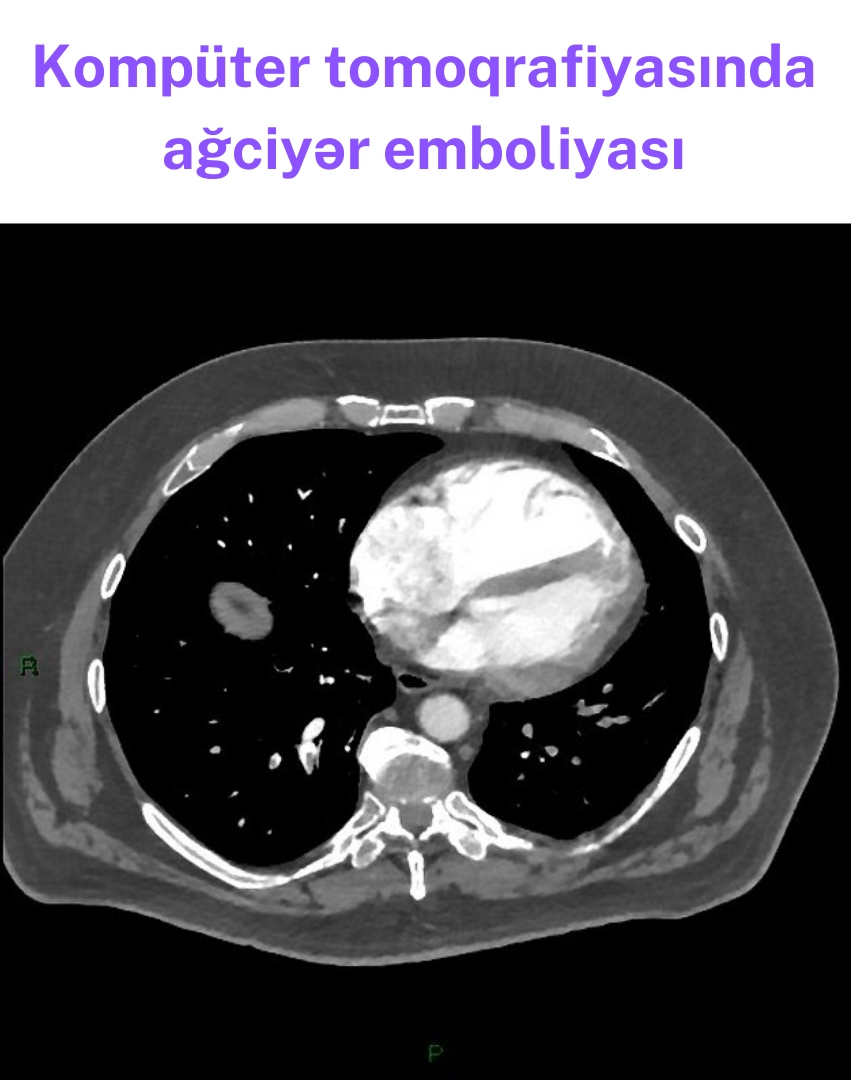

KT-angioqrafiya

İlk seçim metodudur və emboliyanın birbaşa təsdiqi üçün ən dəqiq üsuldur.